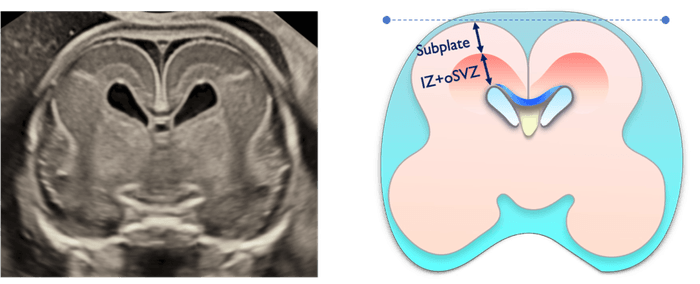

夫 律子院長が発表した研究は、胎児の脳における「サブプレート」と呼ばれる脳層に着目したものです。サブプレートは胎児期の一定の時期にしか観察されることがない特殊な脳層で、ヒトの大脳皮質形成初期においてニューロンの移動や神経回路の形成に重要な役割を果たし、神経発達の鍵を握る構造として注目されています。このサブプレートに着目して実際の胎児での観察実績をもつのは現在のところ世界でもクリフム出生前診断クリニックだけです。※当院調べ

方法:高精度3D経膣脳神経超音波による脳の詳細計測

結果:先天異常を持つ胎児群を複数のグループに分類し、サブプレートの発達パターンを比較分析した結果、グループ間で明確な発達の違いを確認。